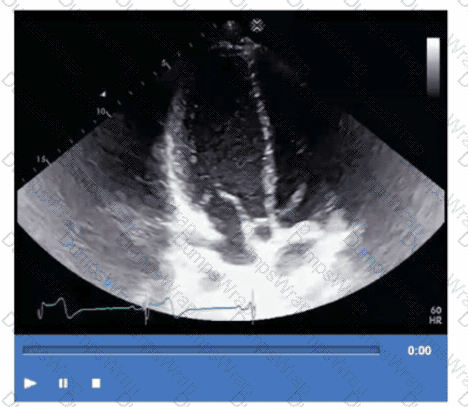

Which is the most likely abnormality represented in these images from a 48-year-old man with shortness of breath?

CExplanation:

The echocardiographic images show prominent trabeculations and deep intertrabecular recesses communicating with the left ventricular cavity, best seen on contrast-enhanced images. This finding is characteristic of left ventricular noncompaction (LVNC), a cardiomyopathy resulting from arrested myocardial compaction during embryogenesis.

LVNC is diagnosed by visualizing a two-layered myocardium with a thin compacted epicardial layer and a thicker noncompacted endocardial layer with deep trabecular recesses. The use of contrast echocardiography enhances endocardial border delineation and recess visualization, increasing diagnostic accuracy.

Loeffler syndrome (hypereosinophilic cardiomyopathy) often shows endomyocardial fibrosis and restrictive physiology but not prominent trabeculations. Hypertrophic cardiomyopathy shows asymmetric septal hypertrophy without deep recesses. Ischemic cardiomyopathy shows wall motion abnormalities but not characteristic trabecular patterns.

These diagnostic criteria and imaging features are well documented in the "Textbook of Clinical Echocardiography" and ASE guidelines on cardiomyopathies and use of contrast echo【16:Textbook of Clinical Echocardiography, 6e†Chapter on LV Noncompaction】【12:ASE Contrast Echocardiography Guidelines†p.180-190】.